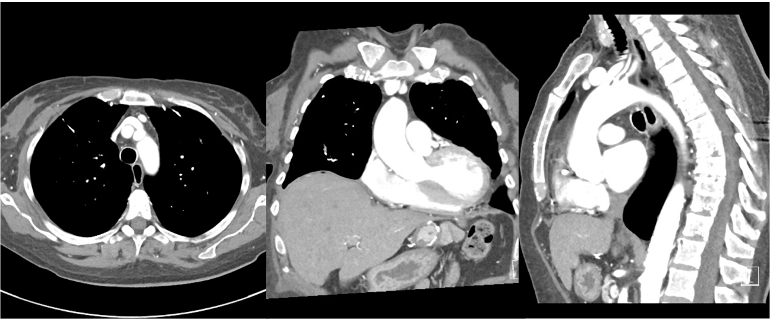

Because we now have 3D images, it is important to define imaging planes since we still view images in 2D slices.

The canonical orientations are axial/transverse, coronal, and sagittal.

Axial/transverse: cross-sections of the body, horizontal slices looking up from the feet. This is the most common view for CT images, although others are also used.

Coronal: view facing the subject.

Sagittal: view from the side of the subject

CT coordinates are typically as follows: Z from superior to inferior(head to feet), X from right to left (patient orientation), and Y from posterior to anterior (patient orientation). Images are typically displayed in transverse/axial, sagittal, and coronal views. Transverse are in the XY plane, coronal in the XZ plane and sagittal in the YZ plane. Transverse are cross sections of the body looking up from the feet, coronal are shown as if facing the patient, and sagittal are from the side of the patient. See imaging planes.